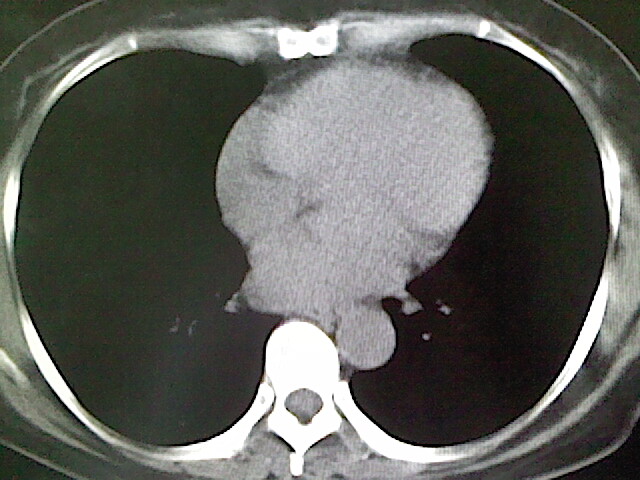

女,52岁,咳嗽,咳痰多日

左下肺陈旧纤维索条!

左肺舌段炎性改变

我见过几例,为炎症后纤维条索

慢性炎症后改变

考虑慢性炎性病灶粘连牵拉改变。

左肺舌叶纤维锁条病变。

左肺上叶下舌段炎症并局部胸膜反应。

左肺舌叶纤维索条影。

左肺舌叶段陈旧性病变

左肺舌段炎性反应。片子的质量太不好了。

左肺舌段炎性

炎性改变

左肺舌叶纤维索条影